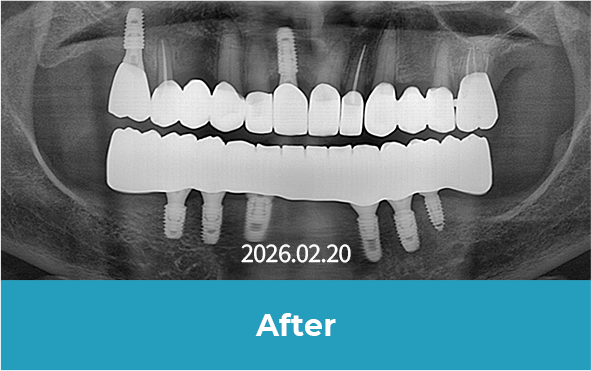

치료 후 사진

[ 환자분의 동의서 작성 후 게시하였습니다 ]